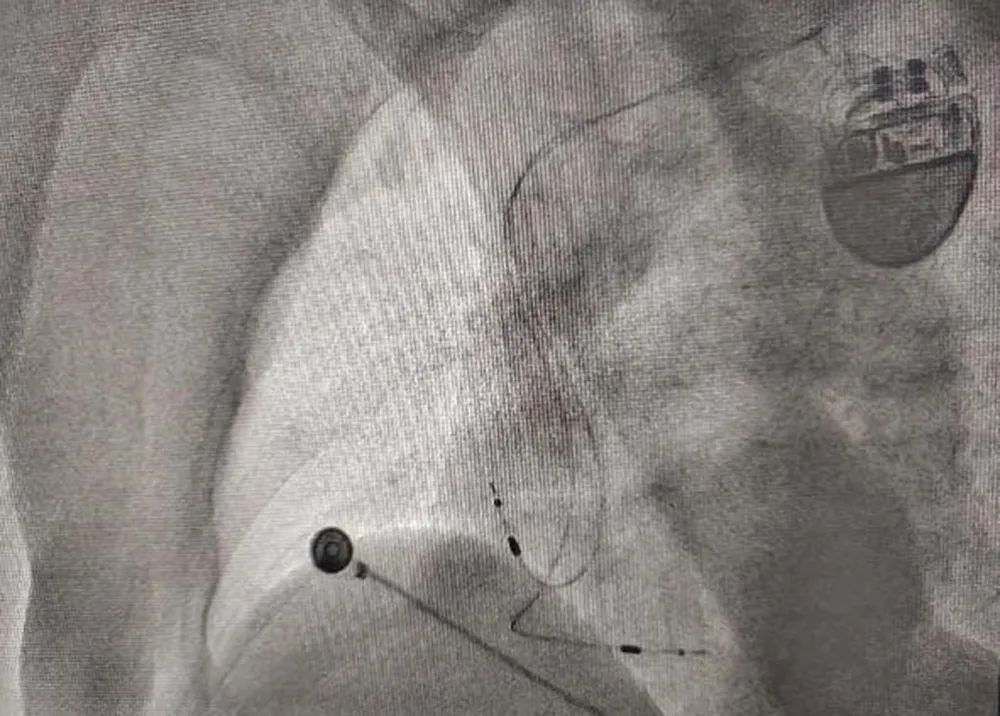

手术当天,患者行局部麻醉,全程处于清醒状态。历时1个多小时,在X线及多导电生理仪指导下,精确找到患者左束支起搏区域,将心室起搏电极头端通过室间隔右室侧旋转到室间隔左室侧左束支区域,起搏夺获左束支及其近端分支,心电图形成类似右束支阻滞的较窄QRS心电图。在实现良好的心室率起搏控制的同时又实现较大化的心室电机械同步。

术后影像